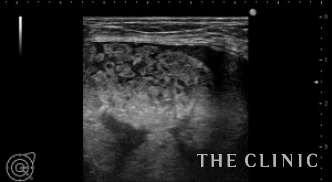

この方は他院でCRF豊胸を受けられました。手術後1年後ぐらいから硬さと違和感を感じ始め、最近は痛みも出現してきたためしこり除去を希望されて当院を受診されました。両側の乳腺下に10㎝を超える大きなしこりを認めます。カプセルに包まれた混合性(充実成分とオイル成分)のしこりです。